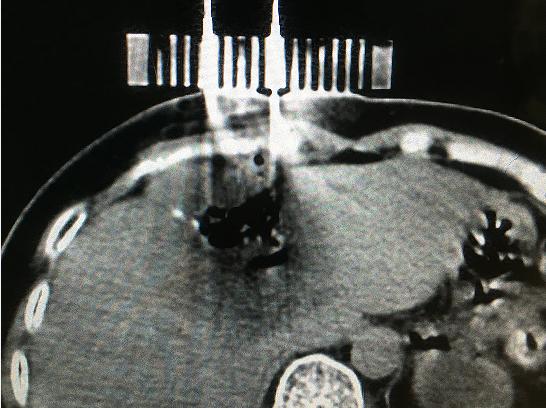

9月11日,醫(yī)院腫瘤科張開賢主任醫(yī)師團隊對一例肝癌術后復發(fā)的患者成功進行了國內首例3D打印共面模板引導下的微波消融術,標志著肝癌進入精準微波消融時代。

患者女性,57歲,肝癌術后5月復發(fā),病灶6.0cmx6.0cm大小,位于肝臟的右葉,靠近隔頂部,經(jīng)過多學科討論,決定實施經(jīng)皮微波消融術,由于腫瘤體積較大,需要同時使用兩根消融天線進行多平面消融,為確保療效,兩根消融天線需要平行等距,但由于肝臟是不斷運動的臟器,徒手操作有一定技術難度,往往需要多次穿刺調整進針方向才能達到上述要求,為此,滕州市中心人民醫(yī)院腫瘤科張開賢主任醫(yī)師團隊借鑒既往采用模板引導放射性粒子植入的經(jīng)驗,創(chuàng)造性地將3D打印模板技術應用于該例患者的消融治療,在模板引導下在兩個平面上平行等距插入兩根消融天線,經(jīng)過18分鐘的消融,腫瘤完全壞死,達到完全消融,患者正在術后康復之中。

3D打印模板引導消融的優(yōu)點:迅速將腫瘤與模板“固定”,防止因肝臟運動導致的穿刺不確定性;確保兩根消融天線平行等距,使熱場分布更加均勻;一次性穿刺布針成功,避免反復穿刺導致的腫瘤種植性轉移;模板對消融天線起到固定,防止因來回移動導致的消融天線位置的改變。據(jù)悉,這是國內首例3D打印模板引導下的肝癌微波消融術,這一技術的推廣應用必將造福更多的腫瘤患者。(腫瘤一科 胡苗苗)